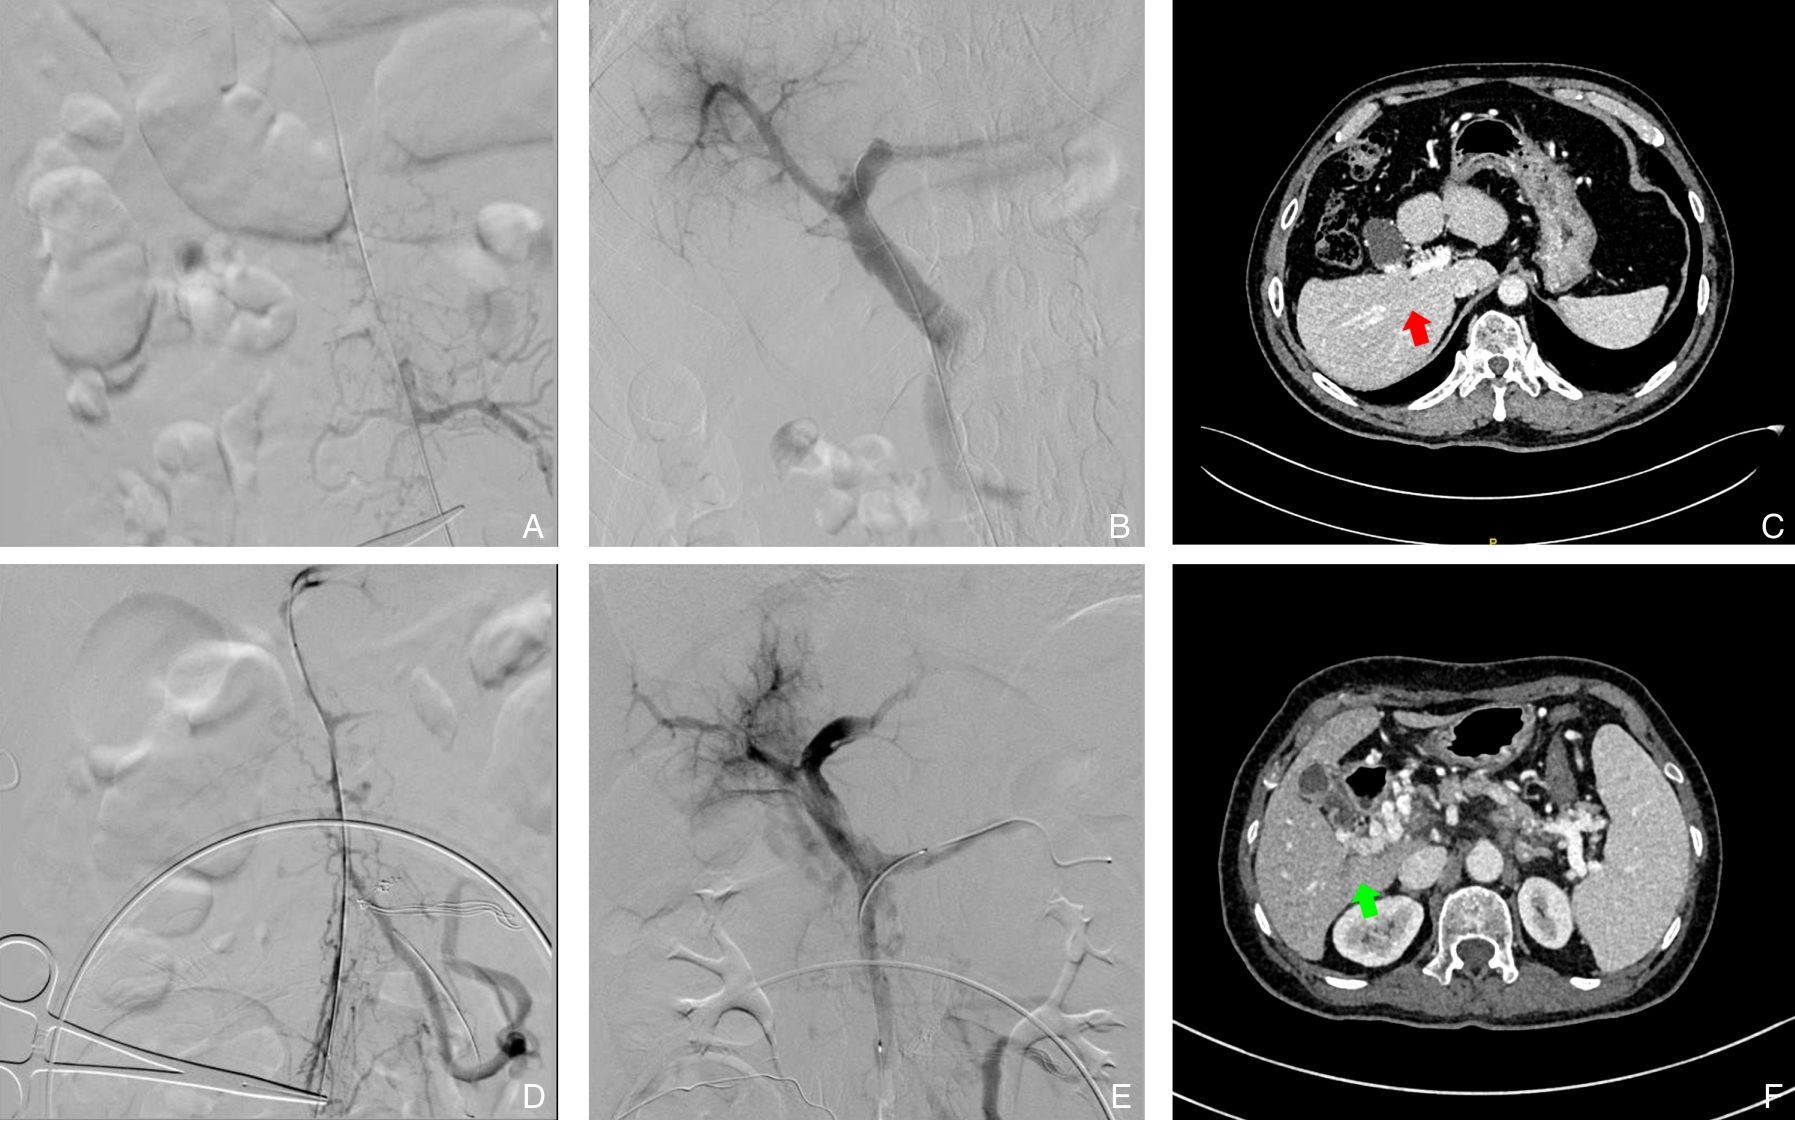

2025, 34(12):2619-2626. doi: 10.7659/j.issn.1005-6947.250158

摘要:背景与目的 急性门静脉血栓形成可导致肠坏死、消化道大出血等严重并发症,单纯抗凝治疗的血栓再通率有限。本文总结经腹小切口直视下穿刺肠系膜上静脉,联合AngioJet溶栓吸栓及球囊扩张治疗急性门静脉血栓形成的临床效果与安全性。方法 回顾性分析2023年7月—2024年12月北京大学人民医院收治的10例急性肠系膜上静脉-门静脉血栓形成患者。所有患者均在全麻下经腹正中小切口直视穿刺肠系膜上静脉,应用AngioJet机械溶栓吸栓联合球囊扩张成形治疗。记录术中即刻血栓清除率、围术期并发症及随访期门静脉系统再通情况。结果 10例患者手术时间中位数为140(110~245)min,不含AngioJet系统相关出血的中位术中出血量为80(50~200)mL;AngioJet机械血栓抽吸系统血栓抽吸时间173(138~296)s。术后即刻血栓清除率Ⅲ级7例,Ⅱ级3例,手术技术成功率为100%。围术期并发症包括腹腔出血1例、切口血肿1例,均经处理后好转。所有患者术后腹痛症状明显缓解,无肠坏死、肠梗阻及急性肾功能不全发生。中位随访时间5个月,门静脉系统完全再通5例,部分再通4例,血栓稳定1例,无血栓新发或复发,随访期内无抗凝相关出血及死亡。结论 经腹直视下穿刺肠系膜上静脉,联合AngioJet溶栓吸栓及球囊扩张治疗广泛急性门静脉-肠系膜上静脉血栓形成安全、有效,可迅速恢复门静脉系统血流,缓解症状并避免肠坏死。